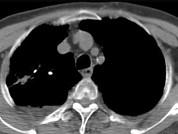

问题 男,76岁,气喘数年,胸痛1个月余,结合影像图像,选择最可能的诊断 ( )

选项 A.右上肺结核球 B.肺间质纤维化 C.右上肺瘢痕癌 D.右上肺错构瘤 E.右上肺肉瘤

答案 C